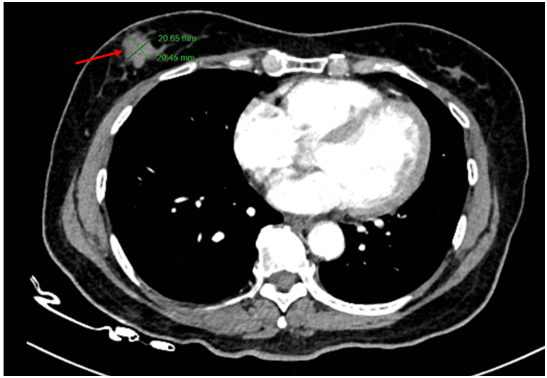

Chụp cắt lớp vi tính lồng ngực có tiêm thuốc: Hình ảnh nốt đặc nhỏ thùy dưới phổi phải. Dải xẹp thùy giữa phổi phải. Nốt ngấm thuốc 1/4 dưới ngoài vú phải đường kính 20mm, bờ ranh giới không rõ, ngấm thuốc sau tiêm.

Hình 3:

Hình ảnh nốt ngấm thuốc 1/4 dưới ngoài vú phải đường kính 20mm, bờ ranh giới không rõ, ngấm thuốc sau tiêm (mũi tên đỏ).